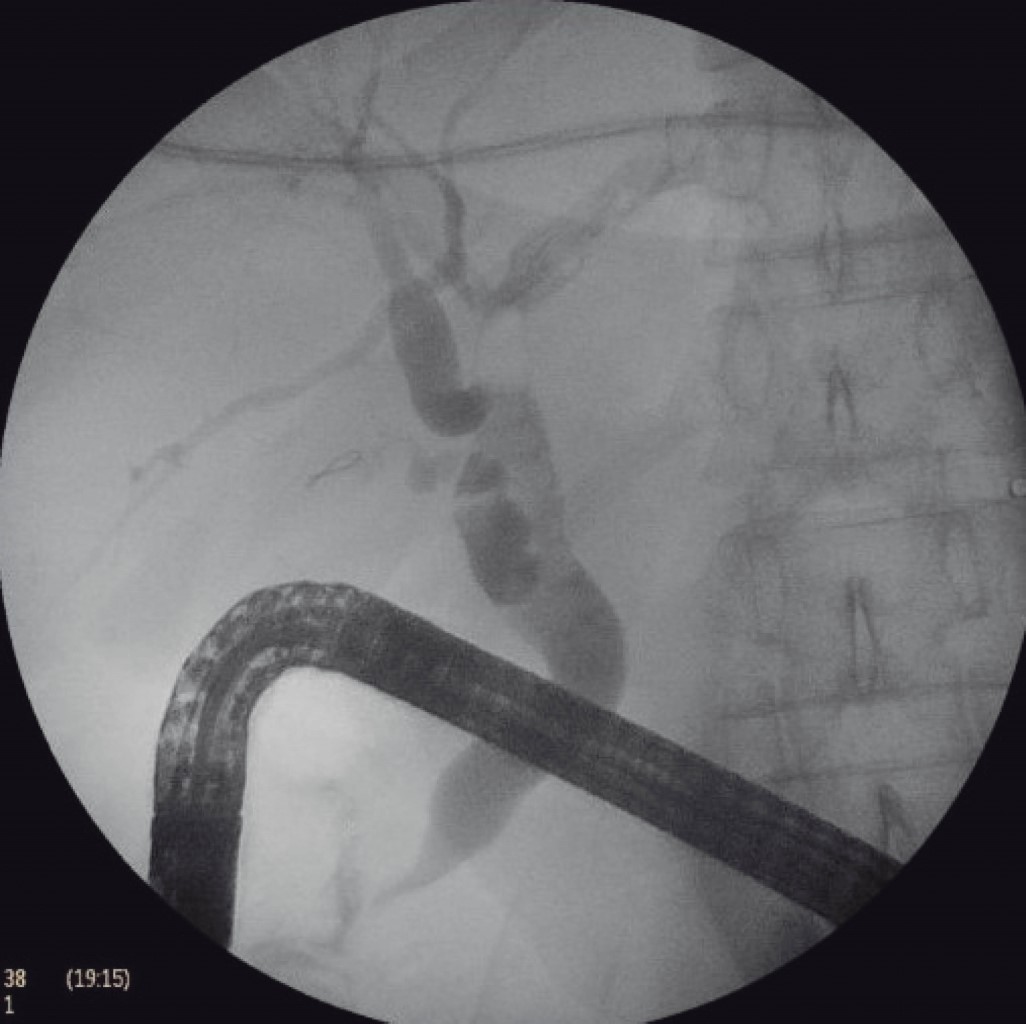

Se colocó a la paciente en decúbito supino con Trendelenburg invertido y bajo efectos de anestesia general, se insertó aguja de Veress en punto de Palmer, se inició neumoperitoneo y se colocó bajo visión directa primer trocar de 15 mm en región supraumbilical paramedial izquierdo seguido de tres trocares más, un trocar paramedial izquierdo de 15 mm colocado de 7 a 10 cm por encima del trocar óptico para la mano derecha del cirujano, trocar paramedial derecho de 5 mm, situado de 7 a 10 cm por encima del trocar óptico para la mano izquierda del cirujano y trocar de 12 mm en hipocondrio izquierdo para el ayudante. Se realizó jareta con PDS 2-0 en antro gástrico y posteriormente incisión gástrica (Figura 2), se insertó a través de gastrostomía el trocar de 15 mm (Figura 3) exteriorizando los hilos de sutura correspondiente a la jareta a través del mismo. El ayudante cirujano y endoscopista avanzó duodenoscopio por medio del trocar de 15 mm hasta segunda porción de duodeno y se observó papila alargada (Figura 4) con múltiples pliegues, posteriormente se canuló de manera selectiva la vía biliar con esfinterótomo y guía de alambre observando avance cefálico de guía, se instiló medio de contraste observando en colangiograma la vía biliar intra y extrahepática dilatada con conducto hepático común y colédoco proximal de 13 mm, colédoco medio 12 mm, colédoco distal de 10.5 mm con un defecto de llenado de 9 mm en su interior. Se realizó esfinterotomía y barrido mediante catéter con balón, se extrajo lito, líquido biliar y contraste. Se infló y ancló catéter con balón, se instiló medio de contraste observando vía biliar permeable sin defectos de llenado (Figura 5). Se procedió a retiro del instrumental con fluoroscopía de control con depuración adecuada de contraste de vía biliar. Se retiró duodenoscopio, se retiró trocar de 15 mm de la gastrostomía y se cerró en dos planos con sutura PDS 2-0 (Figura 6). Se colocó drenaje tipo Blake de 19 Fr hacia la gastrostomía y se exteriorizó por la incisión de trocar en hipocondrio izquierdo, se realizó cierre de heridas por planos y se finalizó el procedimiento sin haber presentado incidentes o complicaciones quirúrgicas. Durante sus primeros dos días de posoperatorio, se mantuvo sin dolor, toleró la vía oral, canalizó gases y el gasto por drenaje escaso con características serohemáticas, por lo que se retiró al segundo día y se decidió su egreso por mejoría, actualmente a varios meses de posoperada se encuentra sin complicaciones.

Figura 5